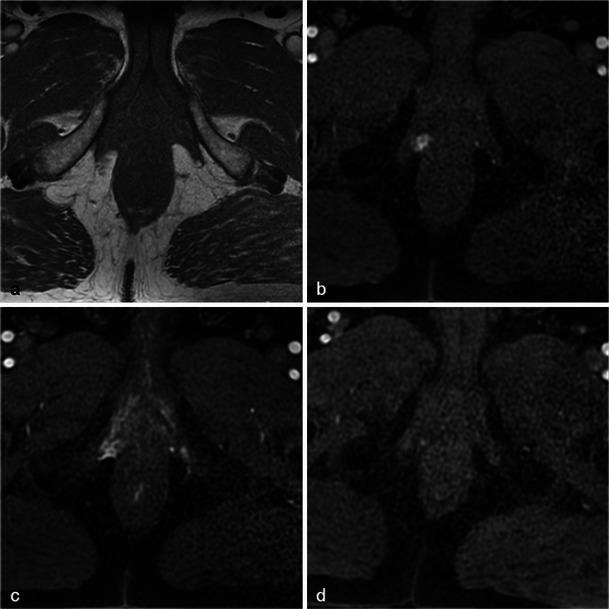

In this technique, a photosensitising agent is introduced intravenously, then activated by local laser illumination to induce tumour necrosis. Treatment efficacy is assessed by magnetic resonance imaging (MRI).

We illustrate specific post-treatment MRI aspects at early and late follow-up with pathological correlations.

• Dynamic phototherapy is a new and promising focal therapy for prostate cancer. • One-week MRI shows increased volume of the treated lobe and large, homogeneous necrosis area. • Six-month MRI shows significant changes of the prostate shape and signal. • Six-month MRI becomes "base line" appearance for further follow-up or monitoring.

在该技术中,将一种光敏剂静脉注射,然后通过局部激光照射激活以诱导肿瘤坏死。通过磁共振成像(MRI)评估治疗效果。

我们阐述了早期和晚期随访时特定的治疗后MRI表现及其与病理的相关性。

• 动态光动力疗法是一种用于前列腺癌的新型且有前景的局部治疗方法。• 一周后的MRI显示治疗叶体积增大以及大片均匀的坏死区域。• 六个月后的MRI显示前列腺形态和信号有显著变化。• 六个月后的MRI成为进一步随访或监测的“基线”表现。